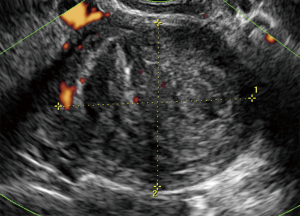

The correct preoperative diagnosis is most important, because an incorrect treatment such as morcellation of the sarcoma or tumor-positive resection margins significantly worsens the prognosis (33). Correct preoperative diagnosis of sarcoma may be difficult. Ultrasound examination, magnetic resonance imaging, computed tomography and positron emission tomography are not reliable in all cases (Figure 1). Ultrasound examination is the first approach, because ultrasound examination is easy to perform, requires no preparation and it is low cost. Symptoms and ultrasound features are often confused with those of benign uterine lesions (uterine myoma) or of other neoplastic lesions (endometrial cancer). In Figure 2 is shown an image of a leiomyosarcoma with ultrasound features of a benign lesion (Figure 2). The first large published series has described the clinical and ultrasound characteristics of 195 sarcomas (7), before several studies were published, but they described few cases, for example, the largest published series of leiomyosarcomas includes eight cases (8). In these studies, the ultrasound variables evaluated were different and often leiomyosarcomas, endometrial stromal sarcomas and undifferentiated stromal sarcomas were not described separately (8-19). In agreement with Exacoustos, Ludovisi et al. described that leiomyosarcomas are large (largest diameter 106 mm) and solitarian lesion, even if they may coexist in same uterus with benign myomas. Leiomyosarcomas are solid mass with inhomogeneous echogenicity with irregular border and irregular cystic areas in half of the cases. Vascularization was minimal or absent in one third of the leiomyosarcomas, in contrast to previous publications (8), probably linked to intra-lesional necrosis (Figures 3,4). Intravenous contrast-enhanced color flow Doppler is an emerging technique in gynecological ultrasound. A prospective study by Lieng suggest that intravenous contrast may help to discriminate between benign endometrial polips and cancer (34). A recent pilot study on a small cohort of patients (35) investigated the use of contrast-enhanced ultrasound for the differential diagnosis of uterine leiomyoma subtype and sarcoma. This study describes an uneven high enhancement without regular border associated with large areas of non-enhancement for sarcomas. Ludovisi et al. introduced a new parameter to describe solid tissue necrosis, defined as “cooked appearance”, a homogeneous avascular area with blurred borders (7) (Figure 5). Exacoustos et al. compared ultrasound features of cellular leiomyomas with those of uterine sarcomas and they demonstrated ultrasound characteristics of “classic” leiomyomas and cellular leiomyomas are different from those of leiomyosarcomas.

The largest published series describing the ultrasound features of endometrial stromal sarcoma includes 48 cases (7) and ten cases (11,17). Kim described 4 patterns of sonographic appearance of endometrial stromal sarcomas: a polypoid mass, an intramural mass, an ill defined large central cavity mass or diffuse myometrial thickening (17). Park described endometrial stromal sarcomas as solid masses with a mean size of 6.2 cm and with internal cystic degeneration in many cases (11). In the series published by Ludovisi et al., endometrial stromal sarcomas appeared solid masses (89.6%) with regular borders (60.4%) and inhomogeneous tissue. This type of sarcoma was less vascularized than the other sarcomas (color-score of 1–2 in 42.6%) (Figure 6).